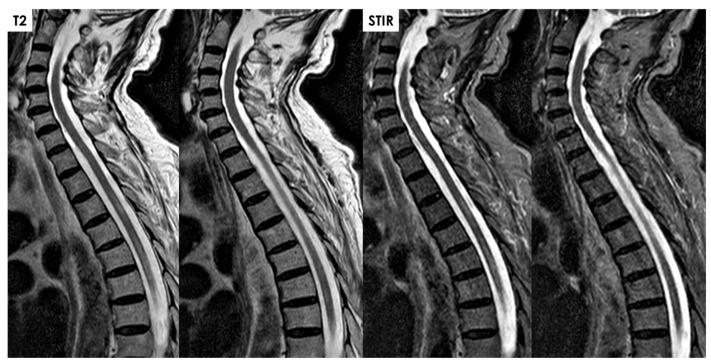

Spinal cord infarction (SCI) of arterial origin is a rare vascular event, and its incidence is probably underestimated. There are no strong epidemiological data, and the diagnostic pathway is complex and sometimes incomplete. Furthermore, many cases may be misdiagnosed as other forms of acute and subacute myelopathies. The focus of this review is the clinical and neuroradiological issues in diagnosing SCI and their respective reliability in a clinical setting. The new proposed diagnostic criteria of SCI, although not covering all aspects, highlight the need for a comprehensive approach, including even atypical cases, as the lack of cord compression on Magnetic Resonance Imaging (MRI) is the only mandatory feature for diagnosis. Some MRI features are supportive of the diagnosis, particularly when the anterior spinal artery territory is involved and diffusion-weighted imaging (DWI) is used. Several etiologies can be considered, considering traditional vascular risk factors and diseases affecting the aorta and its main branches, yet a significant proportion of cases remain without a definite etiology. The strongest predictor of SCI diagnosis is a clinical variable, i.e., a time to nadir of severe deficits < 12 h.

动脉源性脊髓梗死(SCI)是一种罕见的血管事件,其发病率可能被低估。目前尚无强有力的流行病学数据,且诊断路径复杂,有时并不完整。此外,许多病例可能被误诊为其他形式的急性和亚急性脊髓病。本综述的重点是诊断SCI的临床和神经放射学问题及其在临床环境中的各自可靠性。新提出的SCI诊断标准虽然未涵盖所有方面,但强调了采取综合方法的必要性,包括对非典型病例,因为磁共振成像(MRI)上无脊髓受压是诊断的唯一必要特征。一些MRI特征支持诊断,特别是当脊髓前动脉供血区受累并使用弥散加权成像(DWI)时。考虑到传统血管危险因素以及影响主动脉及其主要分支的疾病,可考虑多种病因,但仍有很大比例的病例病因不明。SCI诊断的最强预测因素是一个临床变量,即严重功能缺损最低点出现的时间<12小时。